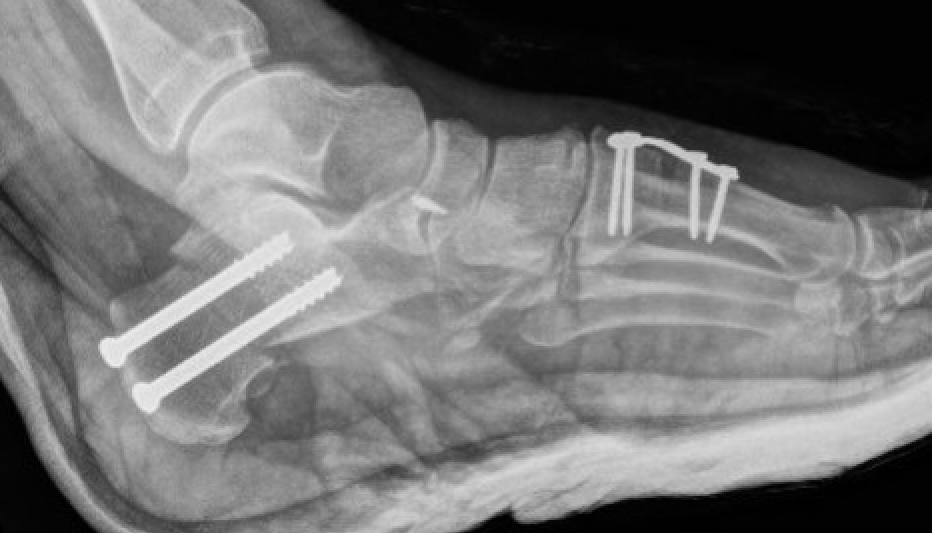

Evans Calcaneal Lengthening Osteotomy

Technique

Incision over anterolateral distal calcaneum

- sural nerve retracted plantar

- P longus retracted plantar

- identify CCJ

- Z lengthen P brevis

- homan retractor in sinus tarsi (between middle and anterior facets)

- homan retractor inferior calcaneum

- K wire into CCJ to prevent subluxation

Opening wedge osteotomy

- 1.5cm proximal to CCJ

- between middle and anterior facets medially

- begin with saw, complete with osteotome

- open 1 cm

- triangular / trapezoidal bone graft (allograft, iliac crest / mid fibular autograft)

- fixation with plate / staple / screw

+/- tendoachilles lengthening

+/- modified Kidner procedure (imbricate spring ligament, Tibialis posterior advancement)